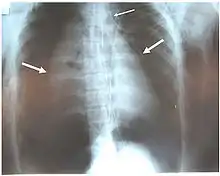

الأشعة السينية هي أولى أدوات التصوير المستخدمة في تشخيص الإصابات الرغامية القصبية. قد لا تظهر أي علامات في الفلم إذا لم يبدي المريض أية أعراض. المؤشرات التي ينظر لها في الأشعة تشمل: تشوه في الرغامى أو خلل في جدار الرغامى نفسها. قد تُظهِر الأشعة تجمع للهواء في منطقة العنق. كما قد تُظهر الأشعة السينية علامات أو إصابات مصاحبة مثل: كسور أو انتفاخات أسفل الجلد. في حال ظهور انتفاخات أسفل الجلد وأظهرت الأشعة السينية وضعية غير طبيعية للعظم اللامي (عظمة في قاعدة اللسان) أعلى الحنجرة، قد يكون هذا مؤشر لإصابة قوية في الرغامى. كما يتم اشتباه هذه الإصابة عندما يبدو الأنبوب داخل الرغامى خارجًا عن مكانه، أو يبدو بالون الأنبوب ممتلئ بشكل يفوق العادة أو بارز في نتوءات مجرى الهواء. في حال كان التمزق على طول الرغامى، قد تنهار الرئة باتجاه القفص الصدري (عكس ما يحدث بالعادة في استرواح الصدر)؛ لأنها تفقد التصاقها بالرغامى والذي بدوره يبقيها باتجاه منتصف الصدر. عند استلقاء الشخص ووجهه باتجاه الأعلى تنهار الرئة باتجاه الحجاب الحاجز والظهر. هذه العلامة تم وصفها في عام 1969 وسميت بالرئة الطريحة، وهي علامة فارقة للإصابات الرغامية القصبية (لعدم تواجدها في حالات أخرى)، لكنها لا تحدث إلا نادرًا. في حالات أخرى، واحد من أصل خمسة أشخاص تعرضوا لحوادث قوية وكانوا بلا علامات في الأشعة السينية رغم وجود إصابة في الرغامى والقصيبات.[17] بينما تتجاوز نسبة اكتشاف الإصابات الرغامية القصبية عبر الأشعة المقطعية الـ90% للحالات الناتجة عن الحوادث القوية. لكن حتى الآن لا يمكن اعتماد الأشعة السينية أو الأشعة المقطعية كبديل عن تنظير القصبات.